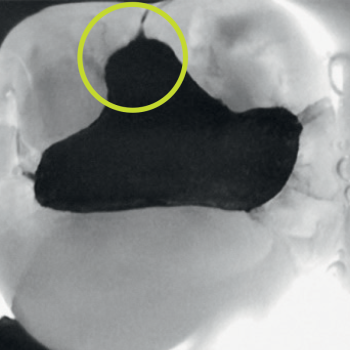

Near-infrared transillumination empowers clinicians to detect proximal lesions that might escape clinical observation and distinguish between lesions confined to the enamel and those that have progressed to the enamel-dentin junction.

Interproximal caries

Occlusal caries

Secondary caries

“It is the best method of caries diagnosis, and you can use it safely. […] [regarding] class II cavities and non-cavitated approximal caries, DIAGNOcam has better sensitivity and specificity than bite-wing x-rays [… ] cavity shape is much better explained and visible.”